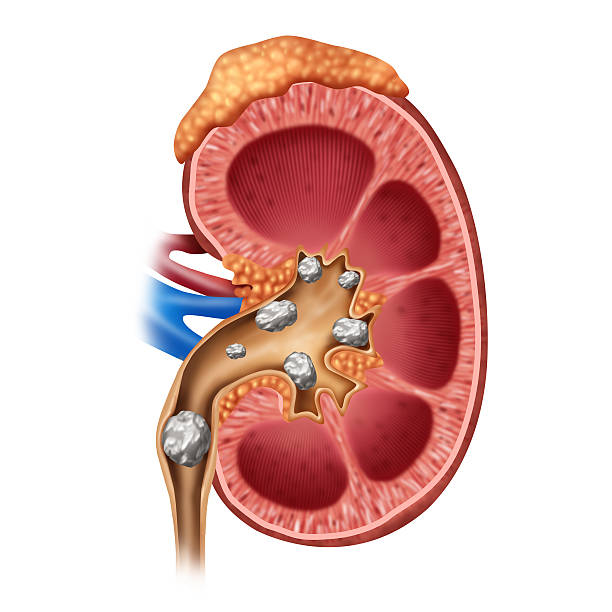

- KESEHATAN